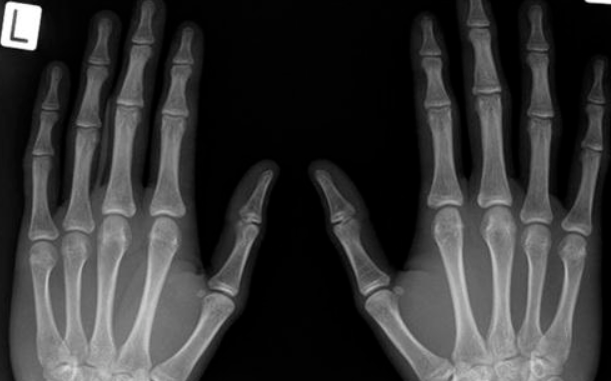

전리방사선 및 비전리방사선의 취급과 방사성동위원소를 이용한 행의학검사와 초음파검사 등 관리 및 취급 업무를 하는 사람을 말합니다. 보통 병원에 가서 엑스레이 검사를 하거나, CT, MRI 검사를 하는 사람들이 방사선사이고, 핵의학과, 방사선종양학과에서 일하는 사람도 방사선사입니다.